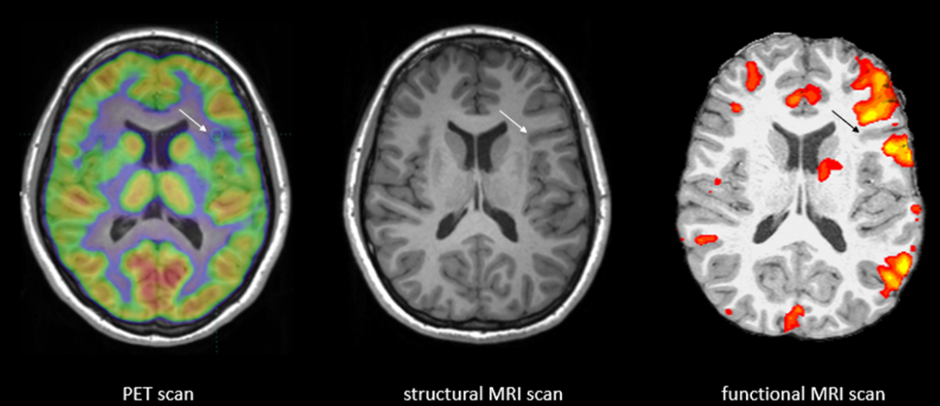

1990년 한 일본계 미국 과학자는 기존에 널리 사용하고 있던 MRI (자기공명영상) 장치를 통해 전에 없던 새로운 시도를 했습니다. 웬만한 종합병원에는 대부분 설치되어 있는 MRI는 엑스레이와 같이 인체 내부 조직을 영상화하여 보여주는 장치로 알려져 있죠. 당시 세계 최고의 전자통신연구소라고 할 수 있는 미국의 Bell Lab에서 연구 중이던 세이지 오가와 박사는 MRI로 생쥐의 뇌를 관찰하고 있었는데요. 한 마리는 100% 산소를 들이마신 쥐이고 다른 한 마리는 일반 공기를 마신 쥐였는데 뇌영상이 전혀 다르게 나왔습니다. 그 이유를 조사하던 중 뇌에 흐르고 있는 혈액의 산소가 녹아 있는 정도(산소포화도)에 따라 신호의 변화가 온다는 것을 알아냈습니다. 산소가 많이 녹아 있다는 뜻은 그 부위가 활성화되어 있다는 것을 의미하므로 영상으로 활성화된 부분을 찾아낼 수 있으며 그 패턴을 활용하는 것입니다. (아래 사진 참조). 이는 마치 열적외선 카메라로 야간에 사람들의 위치를 파악하는 것과 비슷한 개념입니다. 그리고 이러한 MRI 촬영법을 BOLD (Blood-oxygenation-Level Dependent) 이미징 기술이라고 부르게 되었습니다.

image4-2.png 각기 다른 스캔 이미지를 비교 설명하고 있다. 가장 오른쪽이 fMRI 스캔한 이미지.

흥미로운 부분은 BOLD 이미징 기술의 개발 후 수많은 세계적인 뇌과학자들이 이를 이용하여 동물뿐 아니라 사람의 뇌의 이미징에 사용하게 되었다는 것입니다. 환자의 뇌의 활성화되는 부위를 관찰하므로 질병과 연결시킬 수도 있었습니다. MRI에 새로운 기능을 부가했다고 하여 fMRI (functional MRI, 기능성 fMRI)라고 부르고 있습니다. 최근에는 fMRI 통해 사람이 어떤 사물을 관찰하고 있는지 무슨 생각을 하고 있는지에 대한 패턴을 분석할 수 있게 되었습니다. 단적인 예로 영화를 시청하는 사람의 뇌를 분석한다고 합시다. 영상에서 나오는 사물과 내용에 따라 다른 fMRI 이미지가 생성되는데 특정 사물을 볼때 마다 그 이미지의 패턴이 반복적이고 일관되게 나타남을 알게 되었습니다. fMRI는 사람이 보고 있는 사물과 생각하는 것까지 간접적으로 파악할 수 있는 '사람의 마음을 읽는 기계'로 거듭나게 되었습니다. 근래는 컴퓨터 분석 특히 인공지능, 머신러닝을 통해 좀 더 명확하게 분석되고 있습니다.